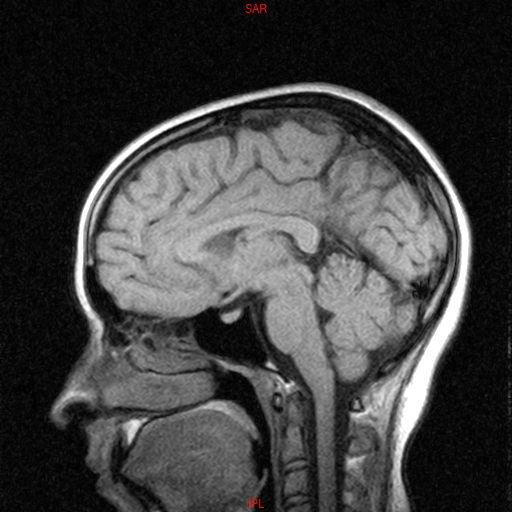

• Resonancia NORMAL CRANEAL T1 SAGITAL